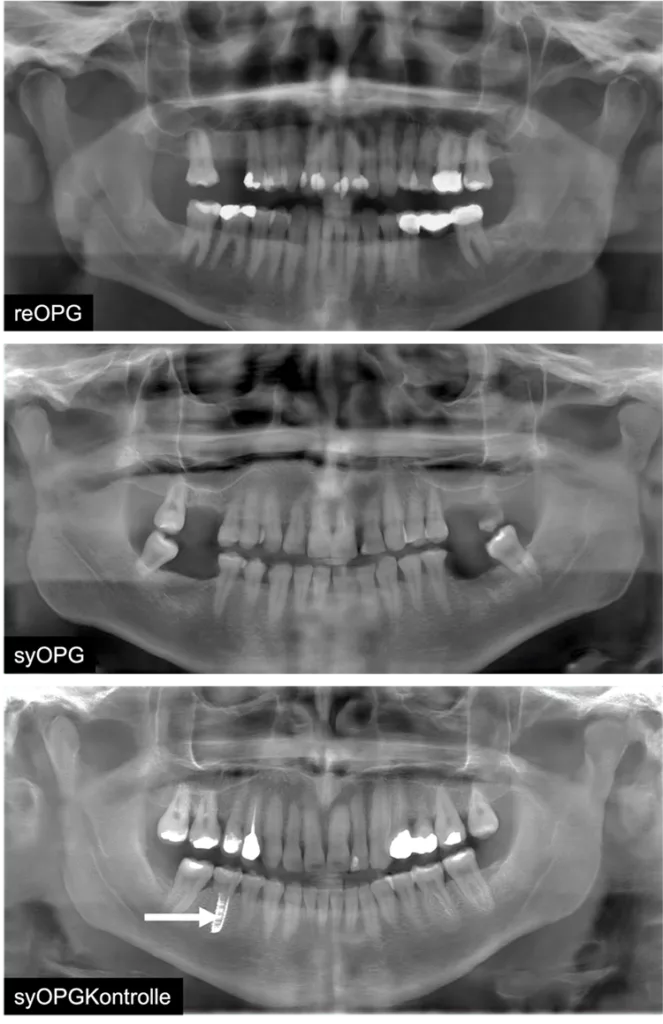

Für die Studie wurden zunächst 9599 reale OPGs als Trainingsdatensatz ausgewählt, um damit GANs, die StyleGAN2-ADA (NVIDIA©), zu trainieren. Hieraus wurden dann 1000 synthetische OPGs erzeugt. Aus diesen wurden 20 syOPGs sowie 5 Kontrollbilder (syOPG-Kontrollen) mit offensichtlichen logischen Fehlern ausgewählt. Weitere 20 reOPGs aus dem Trainingsdatensatz wurden ebenfalls zur Evaluation herangezogen.

In einem umfangreichen, randomisierten, verblindeten Fragebogen wurden 54 approbierte (Zahn-)Ärzt/-innen und 33 Zahnmedizinstudierende gebeten, die Authentizität der Bilder zu prüfen, indem sie die o.g. 45 Bilder entweder als real oder synthetisch bewerteten (Abb. 1 und 2). Zusätzlich wurde ein Einzel-syOPG hinsichtlich spezifischer, diagnostischer Kriterien befundet (Abb. 3). Ferner wurde nach der Selbsteinschätzung sowie der Einschätzung der Bedeutung von synthetischen radiologischen Bildern für den Beruf gefragt. Ein Follow-up-Test zur Überprüfung der Reliabilität wurde ebenfalls durchgeführt.